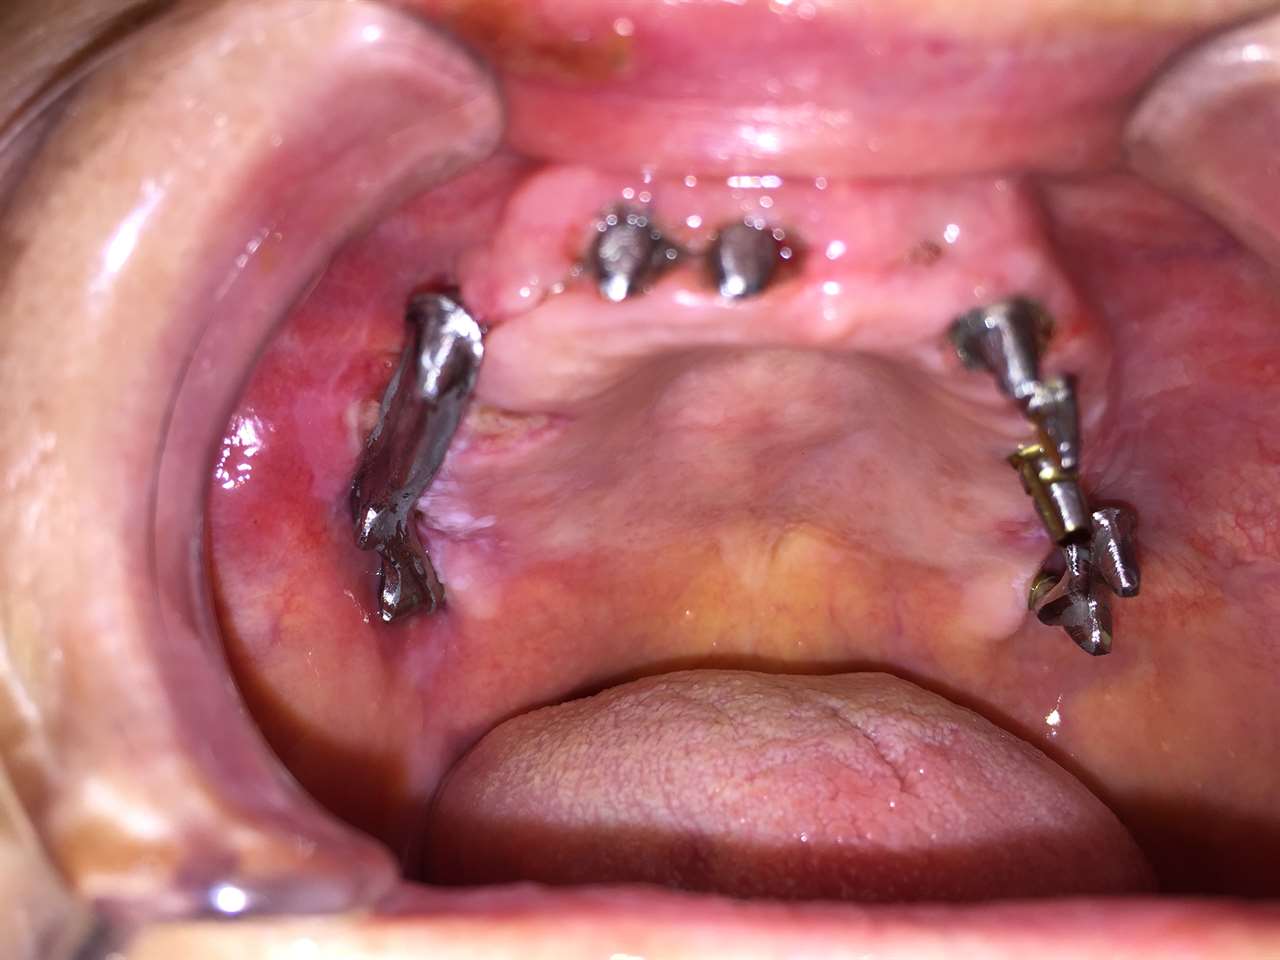

Alsó állcsont teljes rehabilitációja 72 óra alatt

Alsó állcsont teljes rehabilitációja 72 óra alatt, azonnal terhelhető implantátumokkal súlyos paradontitisben szenvedő dohányzó páciens esetében. Az alsó állcsont fogai mind mozogtak az előrehaladott fogágypusztulás miatt.

A fogakat eltávolítottuk, a gyulladt, fertőzött csontot kitakarítottuk, kifertőtlenítettük, majd azonnal implantáltunk.

Svájci, IHDE márkájú, azonnal terhelhető implantátumokat helyzetünk be, és ezekre harmadnapra rögzített, hosszútávú, fémvázas, esztétikus műanyaggal leplezett hidat ragasztottunk be.

Ezt az ideiglenes hidat a sebek gyógyulása miatt használjuk, de tartóssága miatt véglegesként is használható. A legtöbb esetben, ahogy itt is, 6 hónap múlva porcelán hídra cseréljük, a teljes gyógyulás után.